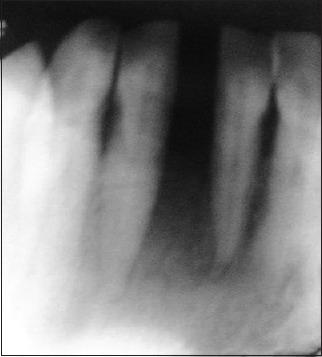

Miller's class III gingival recession is a common entity observed in individuals, posing a difficult situation for the clinicians to treat. Large fenestration defects with cervical abrasion compromise the esthetics resulting in poor prognosis. Obtaining predictable and esthetic root coverage has become an integral part of periodontal therapy. The present case report describes a situation where class III gingival recession with cervical abrasion was seen in the lower central incisors. The patient was successfully treated with a combination of restorations (Filtek Z350(®) composite resin) to fill the defect, followed by fenestration procedure to increase the vestibular depth and subsequently with grafting procedure (soft tissue autograft with bovine-derived xenograft collagen [Bio-oss]). Though the results were not tangible esthetically, it was functionally successful as evidenced during the follow-up period.

米勒Ⅲ类牙龈退缩在个体中很常见,给临床医生的治疗带来难题。伴有颈部磨损的大穿孔缺损会影响美观,导致预后不良。获得可预测且美观的牙根覆盖已成为牙周治疗不可或缺的一部分。本病例报告描述了在下颌中切牙出现Ⅲ类牙龈退缩伴颈部磨损的情况。患者通过联合修复(Filtek Z350®复合树脂)填充缺损、开窗手术增加前庭深度,随后进行植骨手术(自体软组织移植联合牛源异种移植胶原蛋白[Bio-oss])成功得到治疗。尽管在美观方面效果不明显,但在随访期间证明功能上是成功的。